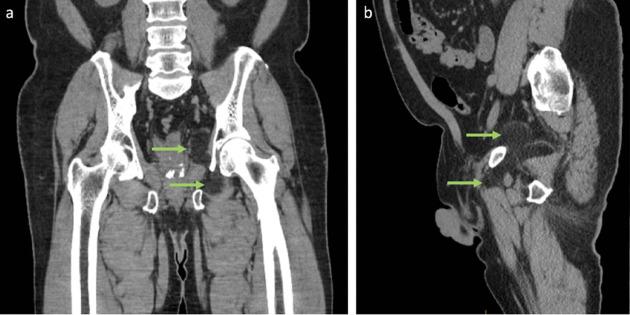

Hibernomas are a very rare and benign soft tissue tumour that originate from brown adipose tissue. While they are not histologically malignant, they may be indistinguishable from aggressive tumours such as liposarcomas on imaging. It is, therefore, important to consider it as a differential diagnosis when a suspicious fatty lesion is seen on imaging. This may prevent unnecessary invasive surgery and patient stress. This paper illustrates the clinical presentation, radiological features, and histological diagnosis of a patient with a rare dumbbell-shaped hibernoma in the pelvis.